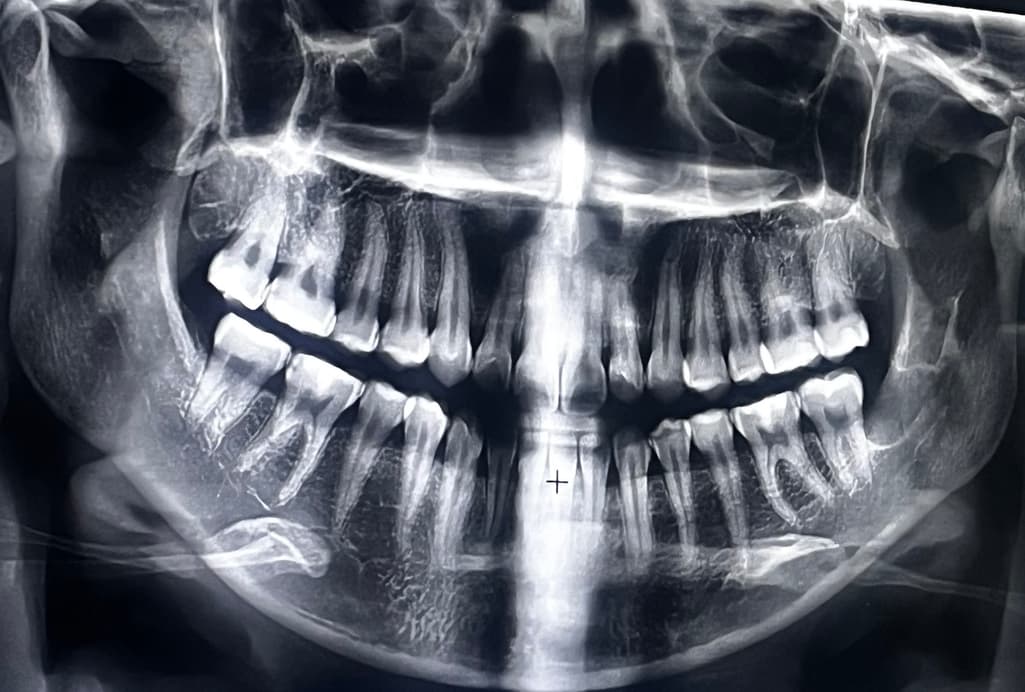

충치진행상태 봐주실 수 있으실까요?

사진촬영하고 전체적인 검진을 받아봤습니다.

기존다니던 A 병원에선 왼쪽•오른쪽 윗 어금니, 왼쪽 아래 어금니 레진으로 충치치료 했습니다.

(다른 곳에도 충치가 있다고 하셨지만 우선 급한3개먼저 치료하자고 하셨으며 나머지 충치는 6개월~1년 후 정기검진때 상황보고 진행하자고 하셨습니다)

오늘 간 B병원에서는 , 오른쪽 아래부분이 신경치료까지 갈 정도로 충치가 있으며 인레이•크라운으로 치료해야될 것 같다고 견적을 내주셨습니다.

오른쪽 위와 오른쪽 아래 어금니 사이에는 충치가 있는 것으로 보입니다. 충치의 여부는 육안으로도 확인을 해야 하기 때문에 사진만으로는 정확한 진단이 어렵습니다. 인접면에 충치가 있다면 보통 인레이 치료 등으로 경계 부위를 만들어주는 경우가 많습니다.

충치가 꽤 커보이는 것이 몇개 보이지만 화질도 그렇고 정확한 진단은 불가능한 상태입니다.

오늘 간 B병원에서는 , 오른쪽 아래부분이 신경치료까지 갈 정도로 충치가 있으며 인레이•크라운으로 치료해야될 것 같다고 견적을 내주셨습니다. -> 이미 신경은 간접 노출되었을것 같습니다 증상있으면 신경치료합니다